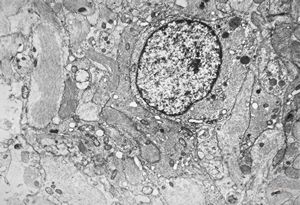

F,50y. | progressive multifocal leukoencephalopathy- viral particles in a glial cell